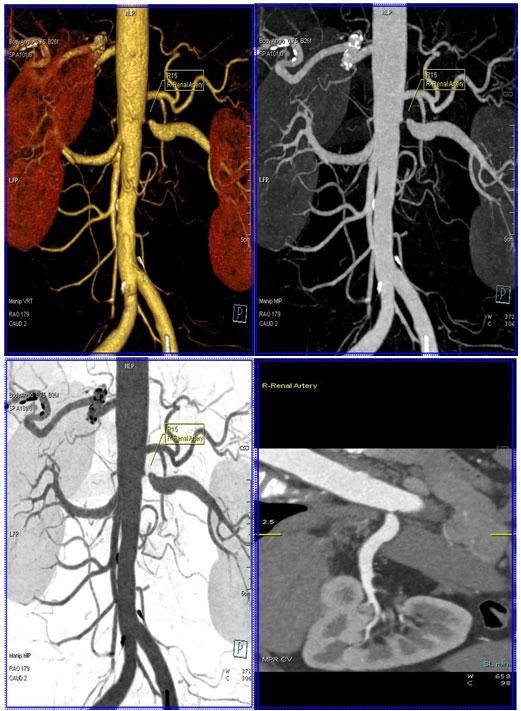

4、腎動脈血管成像(腎動脈狹窄):